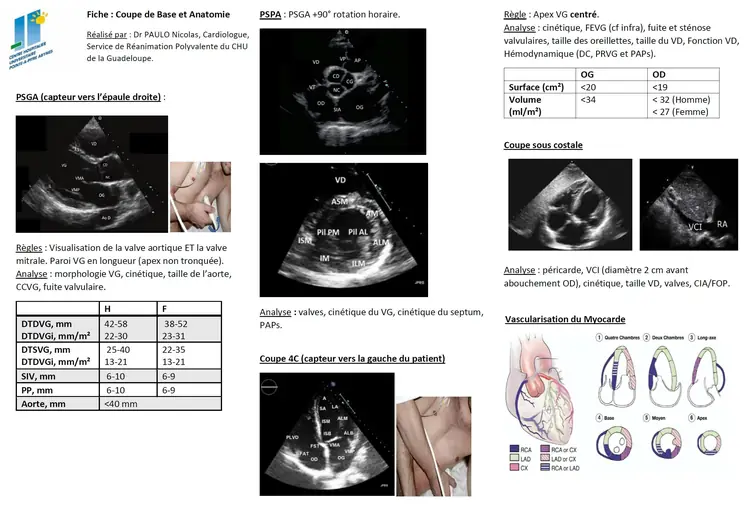

ETT

ETT echographie Echographie échographie cardiaque hémodynamique Hémodynamique hemodynamique echo coeur écho Echo ett